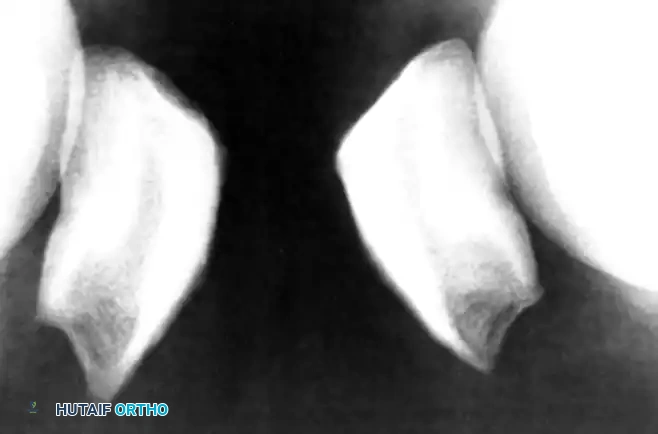

- Radiographs: Anteroposterior, lateral, and tangential (Merchant) views are standard. Early in the disease process, radiolucency at the inferior pole may be noted. With chronic, prolonged symptoms, the inferior pole may become hypertrophied and elongated. A periosteal reaction on the anterior patellar surface (the "tooth sign") and intratendinous calcifications may also be evident.

FIGURE 48-27: Elongation of the lower pole of the patella in an athlete with a long history of patellar tendinosis. Note the structural remodeling secondary to chronic traction.